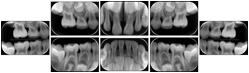

2. A patient requests cosmetic surgery to enhance their facial appearance. The case requires consultation between an orthodontist in New York and an oral surgeon in California. The cephalometric series of 2D projections constructed from a volumetric CT data set that is used for the discussion is arranged by a Structured Display for transfer between the two practitioners.

Cephalometric Series Structured Display

Figure OO-2. Cephalometric Series Structured Display